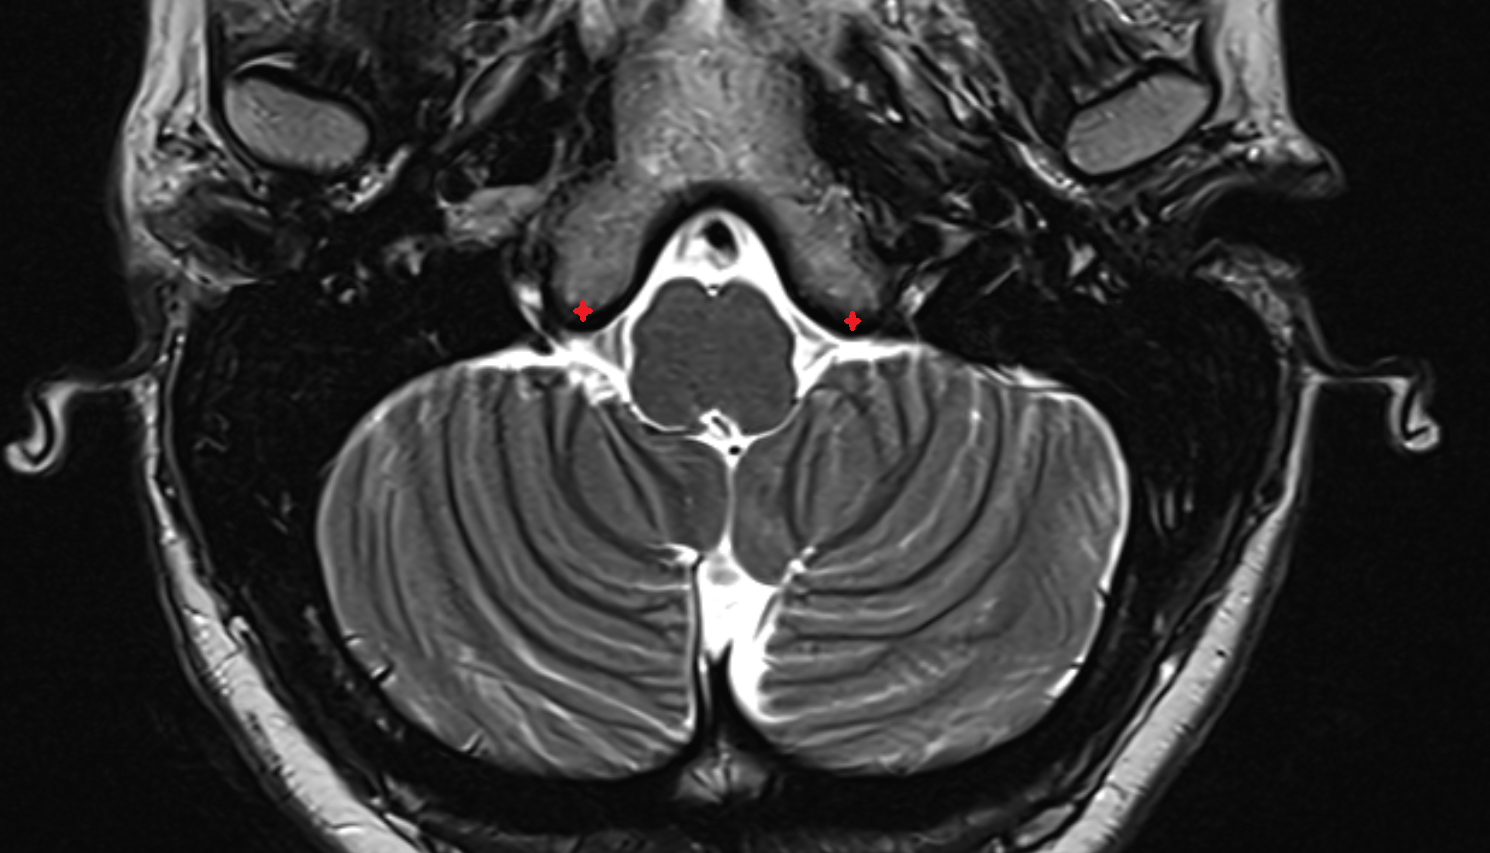

- Cerebellopontine cistern

- Lateral aperture of fourth ventricle (foramen of Luschka)